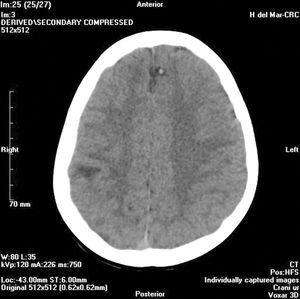

En urgencias se realiza analítica sanguínea (hemograma, bioquímica, ionograma, equilibrio ácido-base y coagulación) que resulta normal; y una TC craneal sin contraste en la que se observa una lesión nodular hipodensa de aspecto quístico con un elemento nodulillar mural sólido, de localización parietotemporal derecha con edema vasogénico asociado (fig. 1). Además se evidencian dos lesiones nodulares hipodensas, probablemente quísticas, con calcio puntiforme mural, localizadas a nivel frontal parasagital izquierdo y parietal derecho, sin edema asociado (fig. 2).

Figura 2.TC craneal. Lesiones nodulares quísticas con calcio mural.